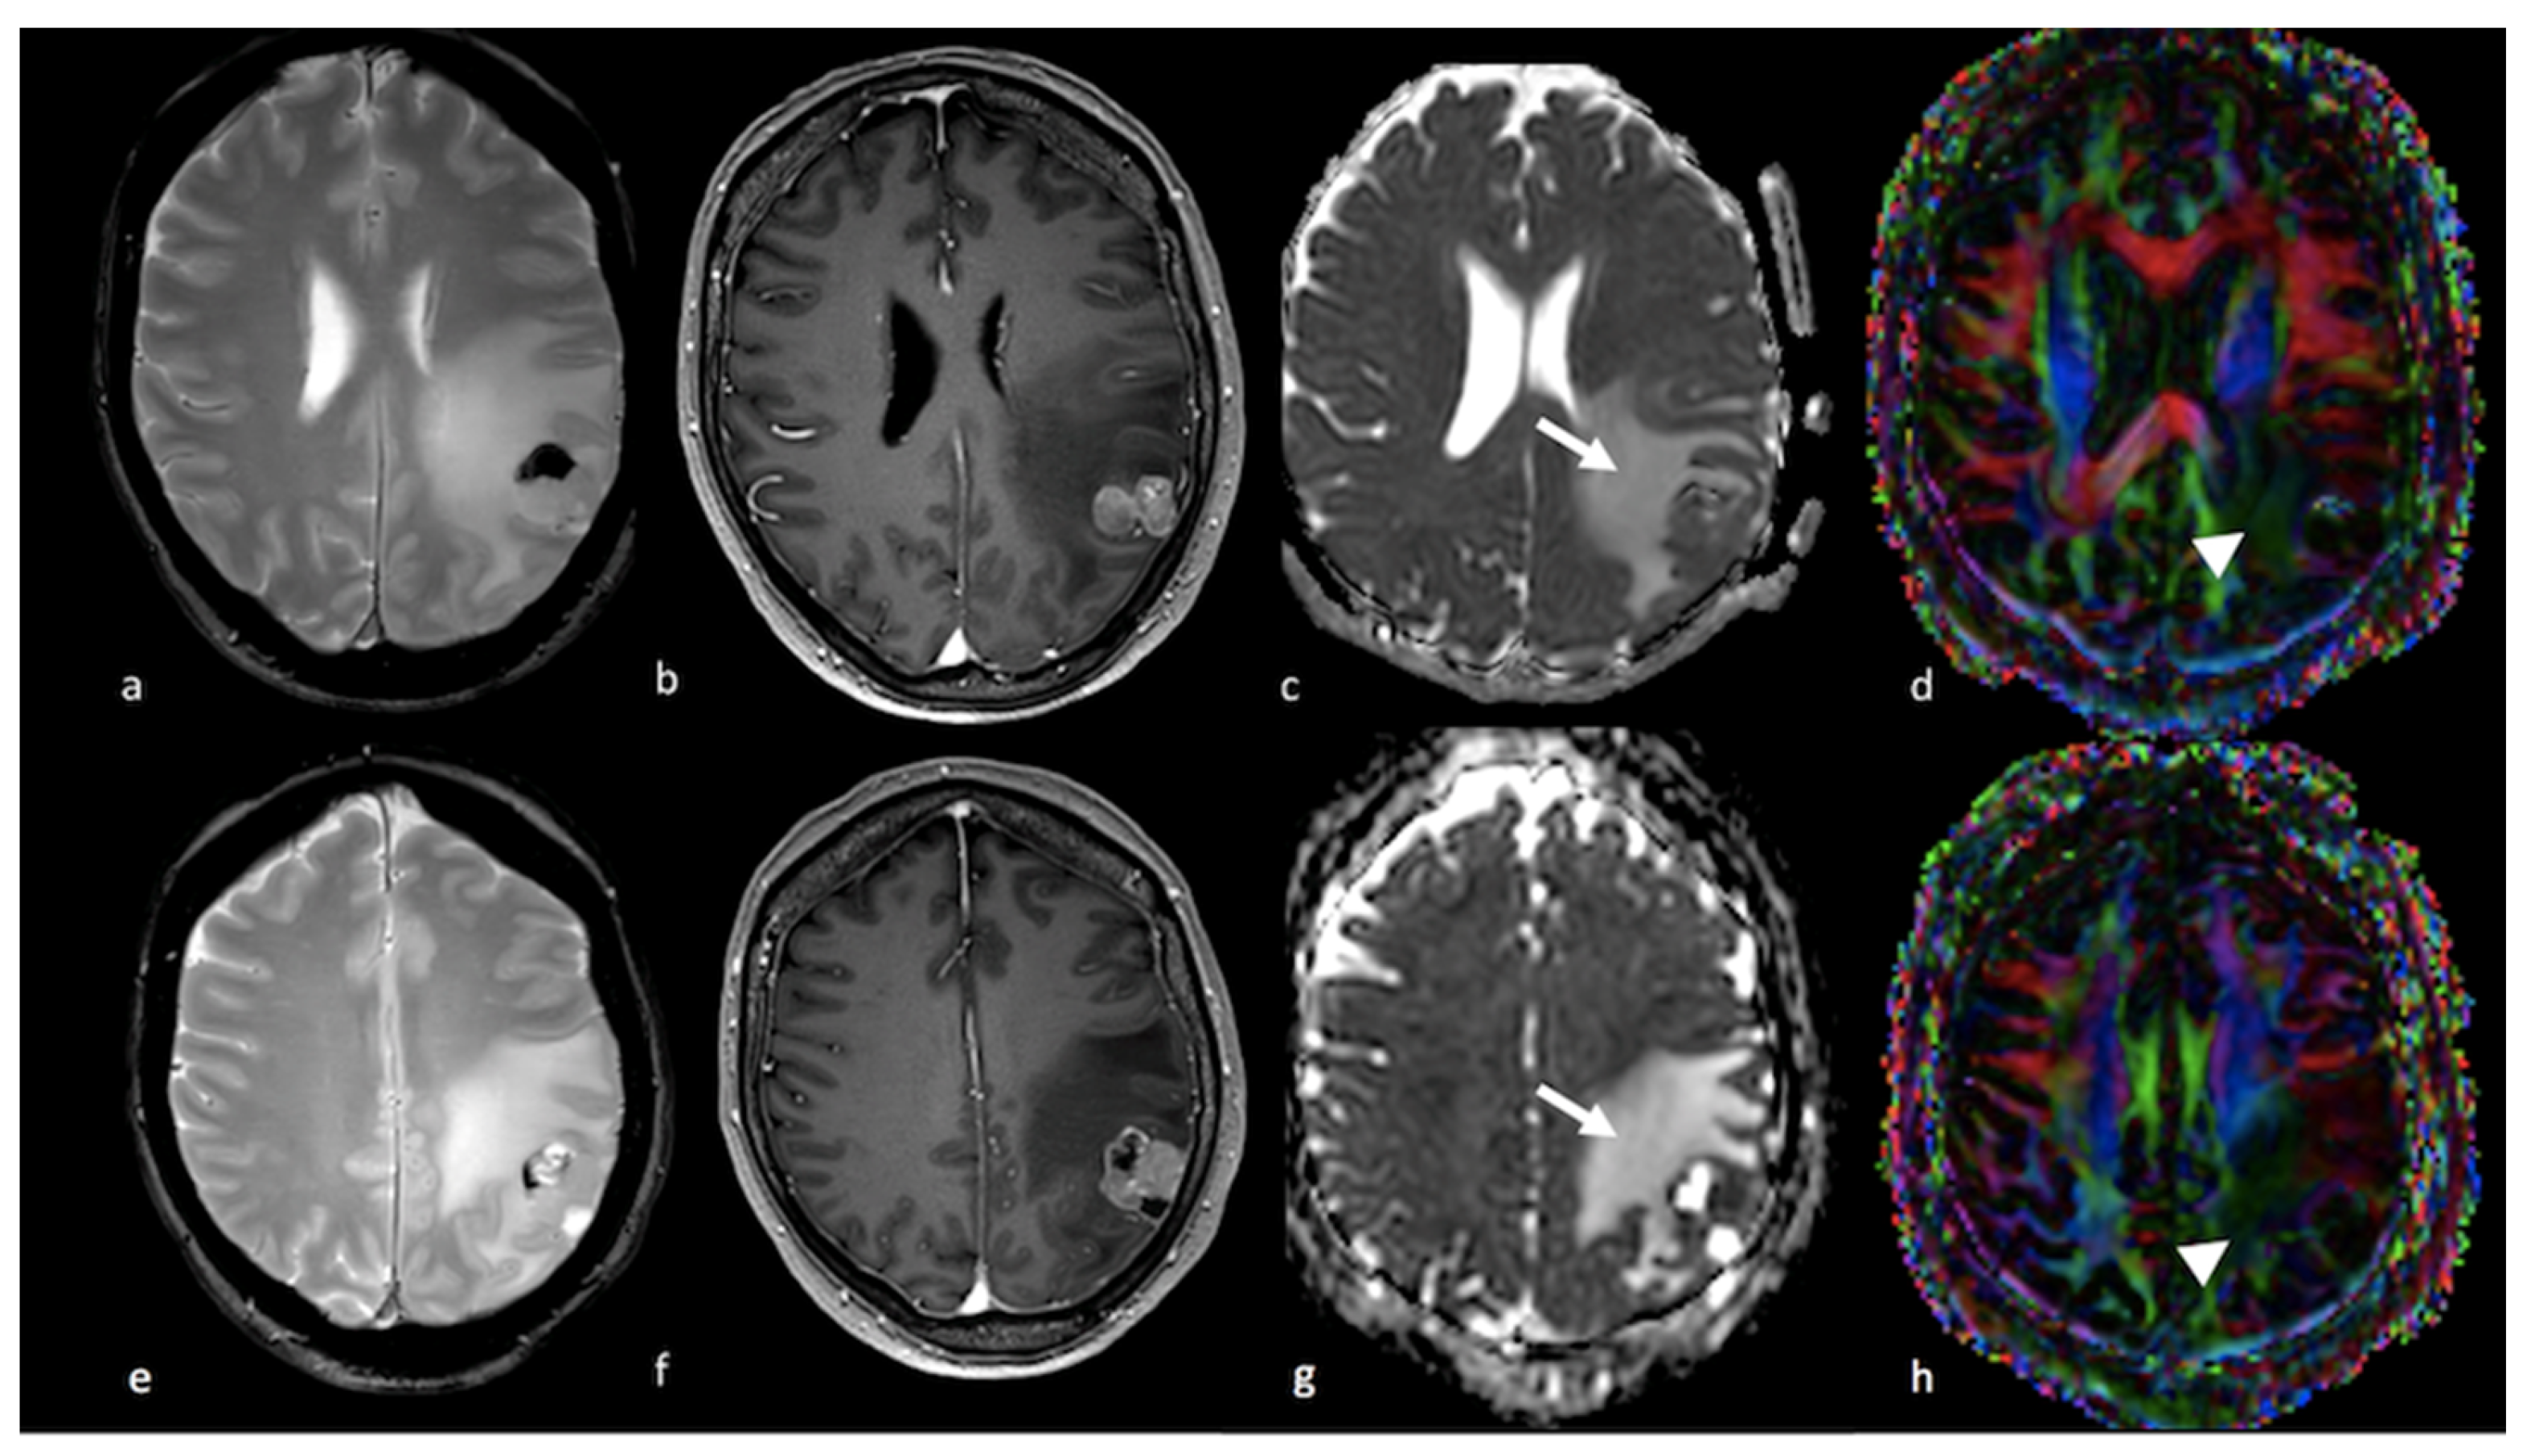

3.2.2. Diffusion Tensor Imaging (DTI)

3.2.3. Diffusion Kurtosis Imaging (DKI)

- Doishita, S.; Sakamoto, S.; Yoneda, T.; Uda, T.; Tsukamoto, T.; Yamada, E.; Yoneyama, M.; Kimura, D.; Katayama, Y.; Tatekawa, H.; et al. Differentiation of Brain Metastases and Gliomas Based on Color Map of Phase Difference Enhanced Imaging. Front. Neurol. 2018, 9, 788. [Google Scholar] [CrossRef] [PubMed]